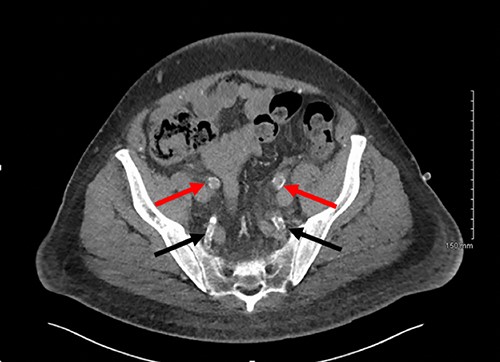

Axial slice of a non-contrast CT AP with red arrows showing calcified external iliac arteries and black arrows showing calcified internal iliac arteries.